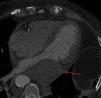

Varón de 80 años, con múltiples factores de riesgo cardiovascular, que ingresa en la unidad de cuidados intensivos por infarto agudo de miocardio sin elevación del segmento ST. Se realiza coronariografía que muestra enfermedad coronaria de tronco izquierdo y descendente anterior que se revasculariza mediante implante de 2 stent farmacoactivos solapados (fig. 1, flecha azul). Para el procedimiento se sonda con una guía la arteria circunfleja (fig. 1, flecha roja). La intervención transcurre sin incidencias, comenzando el paciente tras esta de forma brusca con clínica de insuficiencia cardiaca. Se realiza ecocardiografía transtorácica que muestra a nivel inferior de la aurícula izquierda una masa de 64×40mm de contornos bien definidos e interior ecolúcido con el tamaño reducido de dicha cavidad que compromete el llenado auricular, compatible con hematoma de pared auricular izquierda (fig. 2).